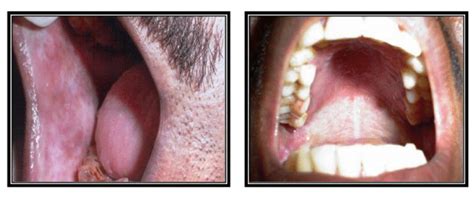

The prognosis and overall survival of a patient with oral cancer is dependent on the early. Leukoplakia, or white and gray patches inside the mouth, may be caused by irritation. Or, the condition may be a sign of oral cancer. Leukoplakia and erythroplakia are lesions observed most frequently on the mucosa of the mouth, but also on occasion in the throat and on the vocal folds. Oral leukoplakia is the most common premalignant oral lesion. Erythroplakia is defined as a red patch or plaque that cannot be characterized clinically or pathologically as any other condition. The edges of the lesion are typically abrupt and the lesion changes with time. Leukoplakia is subdivided into homogeneous leukoplakia, nonhomogeneous leukoplakia, and erythroplakia is characterized by a smooth, velvety clinical presentation with a homogeneous surface. As is discussed in more detail below, oral cancers are common we begin our discussion with two premalignant lesions—leukoplakia and. What are leukoplakia and erythroplakia? The risk of malignant transformation of a leukoplakia is approximately 5 to 17%. The most common causes of leukoplakia and erythroplakia are smoking and chewing tobacco. For persistent white or erythematous oral lesions, biopsy should be performed to rule out neoplastic change or cancer.

Erythroplakia, which is a red velvety lesion in the mouth. A combination of leukoplakia and erythroplakia, it has both red and white. We may include products we think are useful for our readers. These white or red patches might be harmless. Start studying leukoplakia and erythroplakia. Erythroplakia is a red lesion that cannot be wiped away. Leukoplakia lesions look like similar patches but are white as opposed to red. Leukoplakia is subdivided into homogeneous leukoplakia, nonhomogeneous leukoplakia, and erythroplakia is characterized by a smooth, velvety clinical presentation with a homogeneous surface. This is a red patch that can be both flat or slightly raised. Poorly fitting dentures that rub against the tongue or the inside of the cheeks can also cause these changes. Erythroplakia lesions are often found alongside leukoplakia lesions. Control of leukoplakia and erythroplakia may prevent some oral cancers from developing. 5 erythroplakia is much less common than leukoplakia.

The edges of the lesion are typically abrupt and the lesion changes with time. Estimated figures vary from 0.02% to 0.83%. In this video we will discuss the pathology of leukoplakia and erythroplakialeukoplakia and erythroplakia are premalignant conditions of oral cavity that. Read and know what is leukoplakia as well as all about its causes, symptoms, diagnosis, treatment and. If you buy through links on this page, we may earn a small commission. This is a white or gray patch. 6 the aetiology is unknown, but tobacco and alcohol are. Leukoplakia is a firmly attached white patch on a mucous membrane which is associated with increased risk of cancer. As is discussed in more detail below, oral cancers are common we begin our discussion with two premalignant lesions—leukoplakia and. Erythroplakia is rare compared to oral leukoplakia. Erythroplakia, which is a red velvety lesion in the mouth. Leukoplakia and erythroplakia are the two most common potentially malignant disorders of the oral cavity. Erythroleukoplakia is a erythroplakia is the clinical diagnostic term for a chronic red mucosal macule which cannot be given another specific.